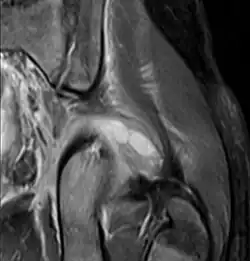

| Transverse T2 magnetic resonance imaging section through the hip region showing abscess collection in a patient with pyomyositis. | |

Axial T1 weighted fat suppressed post IV gadolinium contrast enhanced MRI image showing a mutliloculated bacterial abscess in the left gluteal muscle which grew Staphylococcus aureus (methicillin sensitive) thought to be due to tropical pyomyositis.

Coronal fat suppressed post contrast image showing a multiloculated bacterial abscess in the left gluteus minimus muscle due to tropical pyomyositis.